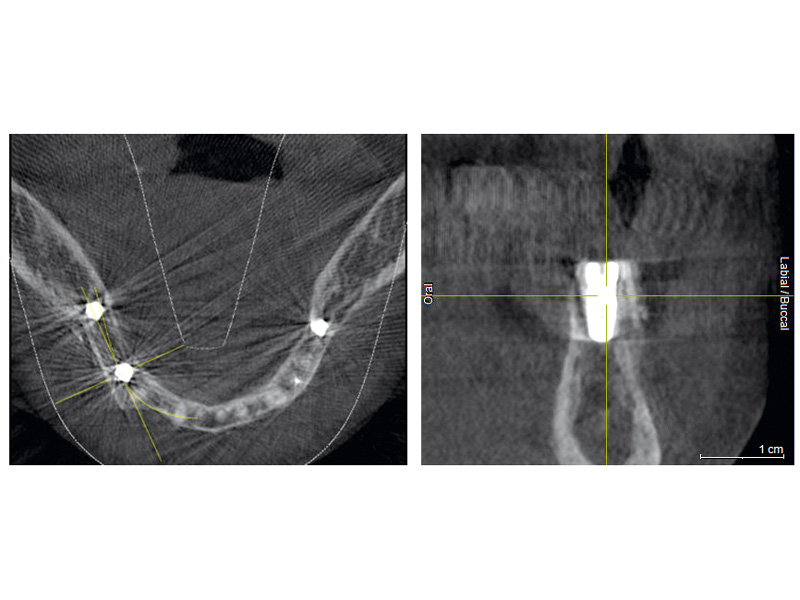

08 / 20 - CBCT recording after the augmentation shows the cortical plate about 3 to 4 mm distant from the host boneHorizontal ridge augmentation with maxgraft® cortico - M.Sc. E. Kapogianni

16 / 20 - CBCT after the implantation shows position of the implant within vital bone tissue and the adjacent allogenic cortical plateHorizontal ridge augmentation with maxgraft® cortico - M.Sc. E. Kapogianni